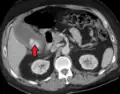

Right upper quadrant abdominal ultrasound is most commonly used to diagnose cholecystitis.[1][26][27] Ultrasound findings suggestive of acute cholecystitis include gallstones, pericholecystic fluid (fluid surrounding the gallbladder), gallbladder wall thickening (wall thickness over 3 mm),[28] dilation of the bile duct, and sonographic Murphy's sign.[13] Given its higher sensitivity, hepatic iminodiacetic acid (HIDA) scan can be used if ultrasound is not diagnostic.[13][14] CT scan may also be used if complications such as perforation or gangrene are suspected.[14]

Acute cholecystitis with gallbladder wall thickening, a large gallstone, and a large gallbladder- Significant gallbladder wall thickening[29]

- Significant gallbladder wall thickening[29]